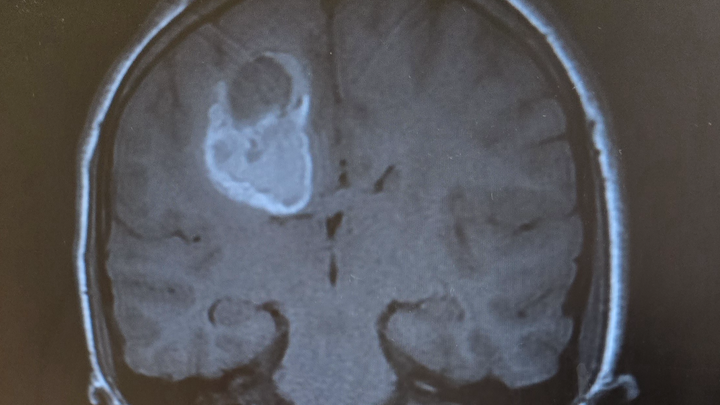

Our world has been turned upside down. Our 13-year-old son, Mason, has recently been diagnosed with a very large 4.3 cm mass in his brain with significant swelling that has hemorrhaged and is now facing brain surgery on January 7th.

No child should ever have to endure something like this, and no parent should have to watch their child go through this. Within a week's time span, Mason lost all movement and control of the left side of his body. He was rushed to multiple doctors before finally getting some answers. He has a Cavernoma. It is an abnormal cluster of blood vessels with slow-flowing blood. This is what causes the neurological symptoms he is having.